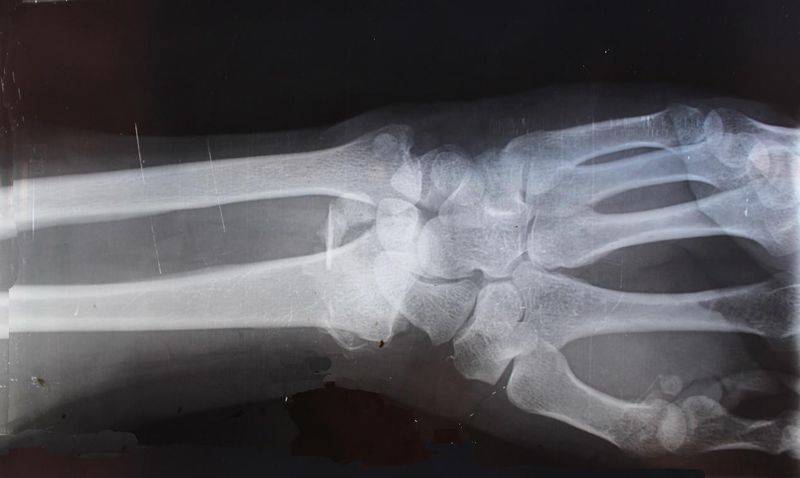

图片:X光医学影像(图源:Unsplash)

图片:X射线(图源:pixabay)

德国物理学家伦琴于1895年发现x射线,法国和波兰物理学家居里夫妇于1898年发现镭,不久就广泛应用于临床诊断。X射线成为诊断疾病的有力工具,镭则用于治疗癌症。免疫学开始成为系统的科学是与19世纪后期微生物学的发展紧密相连的。20世纪20年代初,科学家们先后发现免疫血清在体内和试管中可以凝集细菌和溶解细菌,进而发展到对病原微生物的鉴定和传染病的诊断。